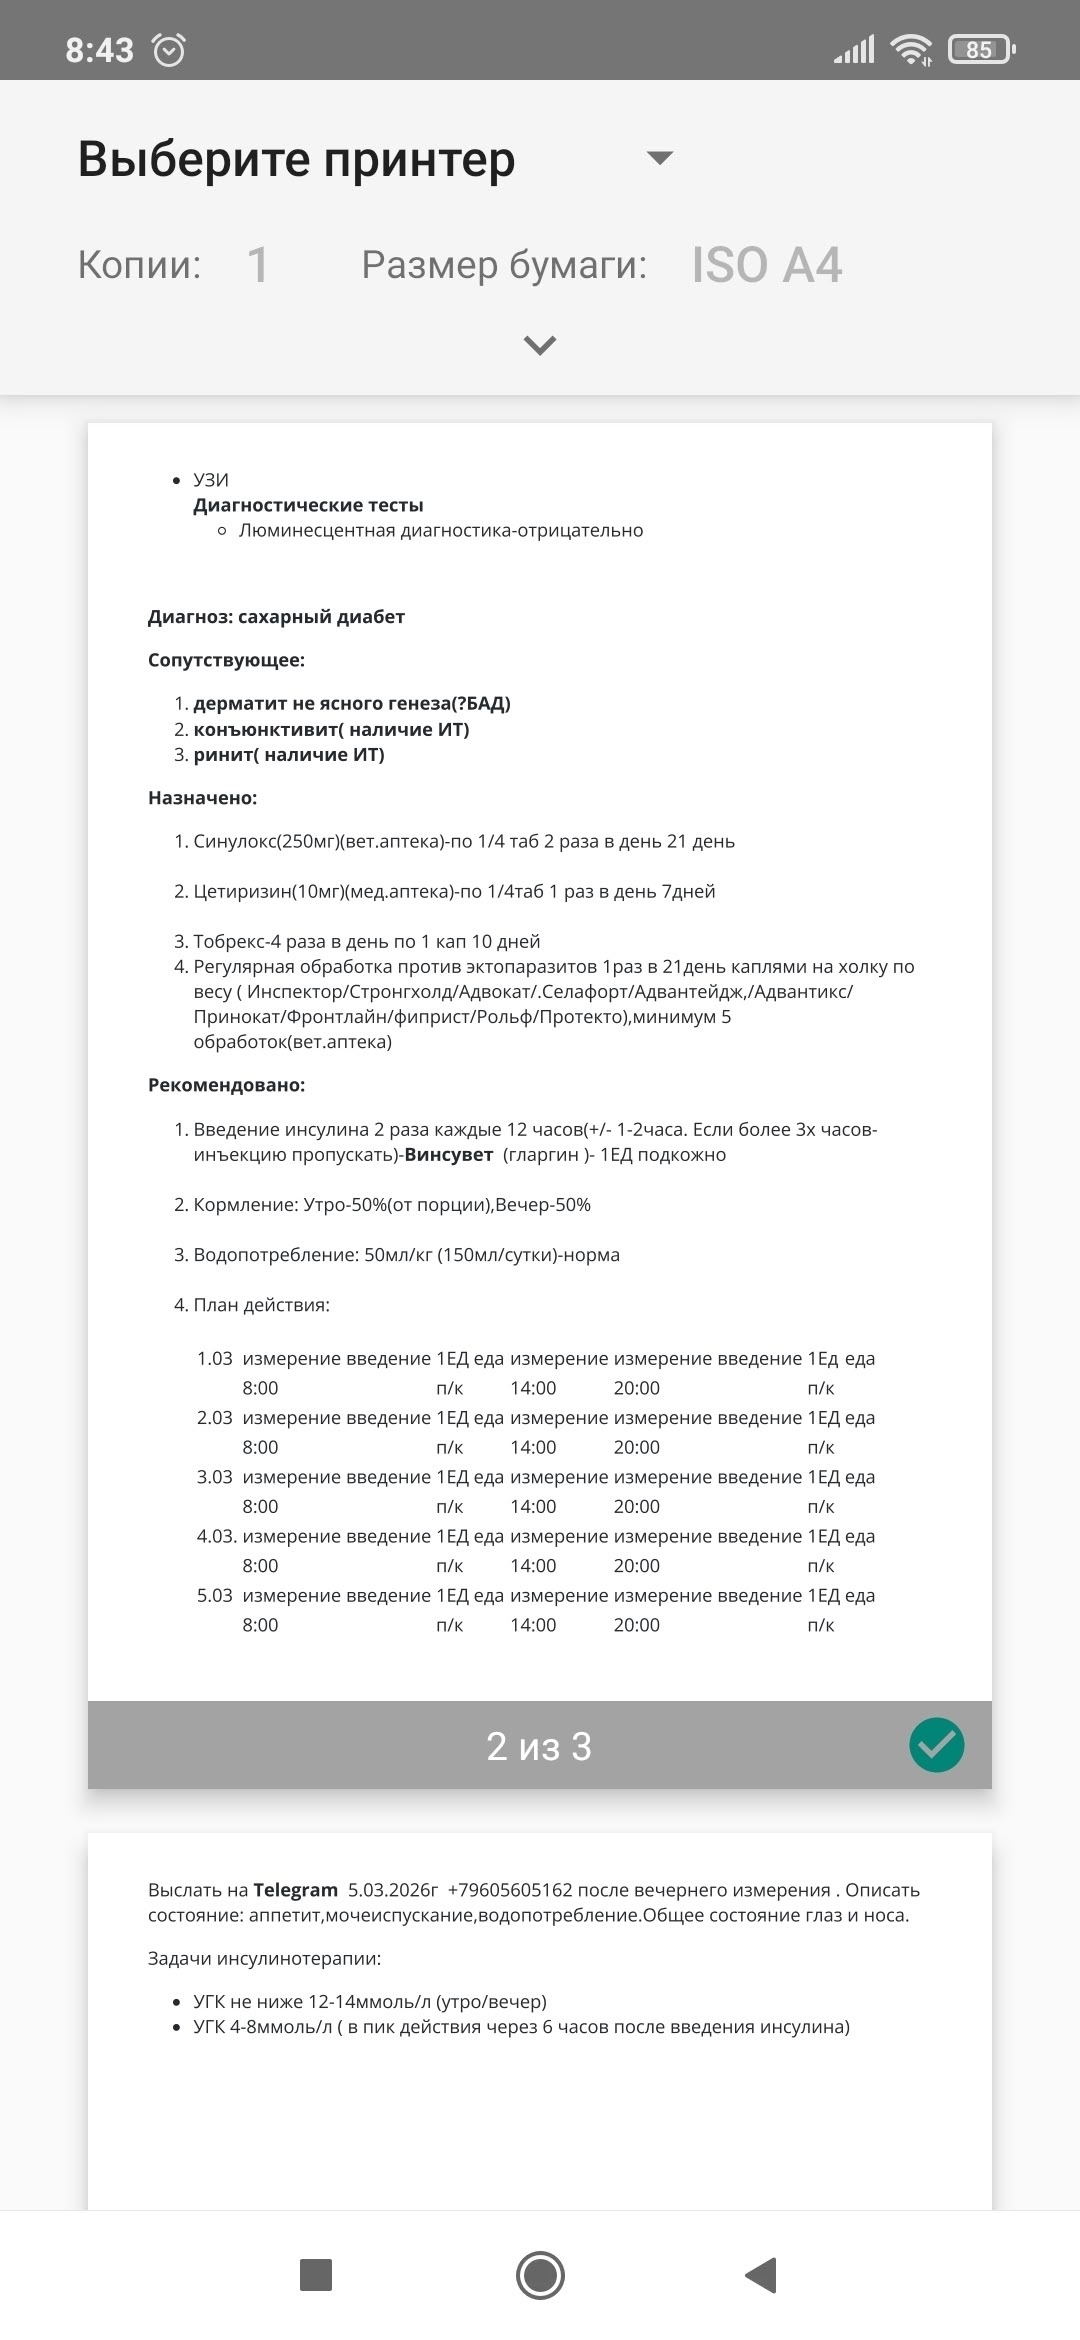

Она сама пришла к нам за помощью, по результатам анализов, карцинома😱Удалили слуховой проход, ушко оставили и зашили, стерилизовали, вылечили от лишая, по рентгену пуля в носу, но и это ещё не всё, диабет, сахар 19, 21😱 Сейчас Мусенька на передержке с медуходом на 1 месяц, для подбора дозировки инсулина и стабилизации сахара 💔Поэтому просим всех неравнодушных о помощи 🙏❤

❗Мусе ежедневно нужен влажный корм 4 пакетика Роял Канин или Брит (предпоследние 2 фото), за месяц получается очень большая сумма!